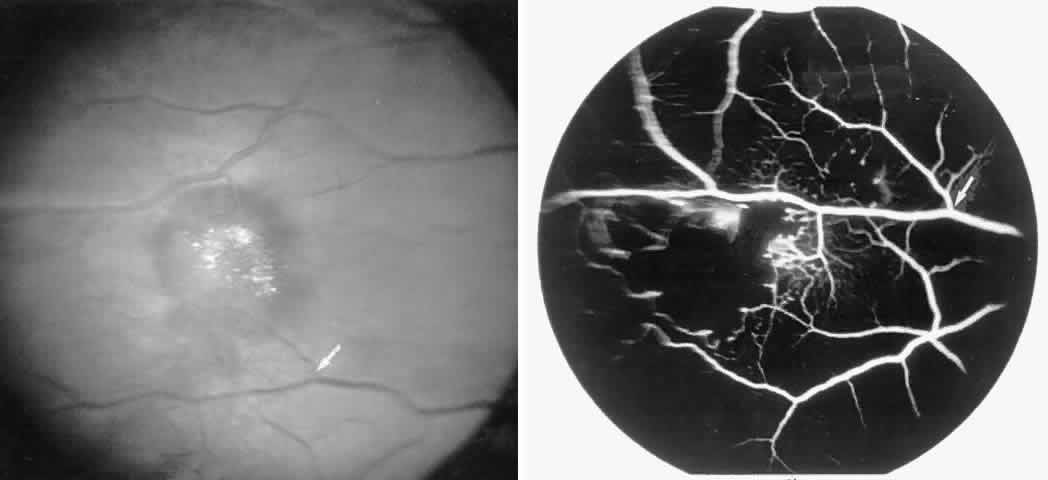

Occlusions of the fine vasculature of the macular and perimacular area have been reported in 10% to 40% of patients with sickle cell disease.18,83,91–99 In the acute phase, the occluded vessel will have a dark red appearance and may appear as a dark line on fluorescein angiography (Fig. 9). Nerve fiber layer infarcts (cotton-wool spots) are seen (see Fig. 8D and E;Fig. 10).100

Fig. 9. A 27-year-old man with homozygous sickle cell anemia. A. Fluorescein angiogram of the right eye shows multiple arteriolar occlusions temporal to the fovea (arrows). B. Same area 6 months later shows more extensive occlusions. The black arrowheads (A and B) identify corresponding arteriolar bifurcation.

Fig. 10. A 33-year-old woman with SC disease and stage III sickle cell retinopathy. A. Photograph of the right eye shows a cotton-wool spot with a dark segment identifying the occluded vessel (arrow). B. Fluorescein angiogram demonstrates nonfilling of the occluded vessel (arrow). C. Eighteen months later, the occluded vessel is still visible (arrow). D. Fluorescein angiogram demonstrates that there is still nonfilling of the vessel (arrow).

Other macular and perimacular changes include microaneurysm-like dots, dark and enlarged segments of arterioles, hairpin-shaped venular loops, pathologic avascular zones, and widening and irregularities of the foveal avascular zone (Figs. 11 and 12). In the Jamaican cohort study evaluating children with homozygous sickle cell anemia and SC disease between the ages of 5.0 and 7.5 years of age, no pathologic avascular zones could be identified despite a high incidence of peripheral vascular closure.31 In evaluating patients with homozygous sickle cell anemia, no relationship between ISC counts and macular abnormalities or visual acuity could be found.101 Using fluorescein angiography, investigators have found the foveal avascular zone to be significantly larger in eyes with clinical evidence of sickle cell maculopathy as compared with normal eyes and eyes without clinical evidence of sickle cell maculopathy.102–104